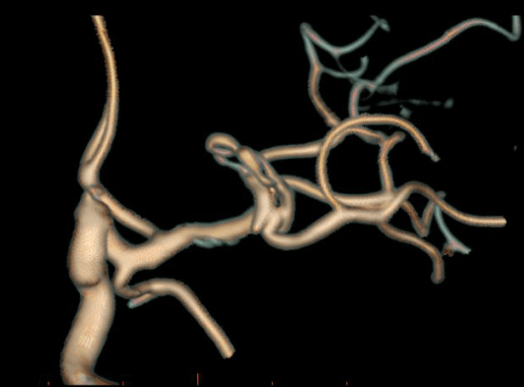

Clipping di aneurisma complesso M1-M2 di sinistra – ricostruzione biforcazione arteria cerebrale media

Aneurisma Biforcazione ACM – Vito Fiorenza